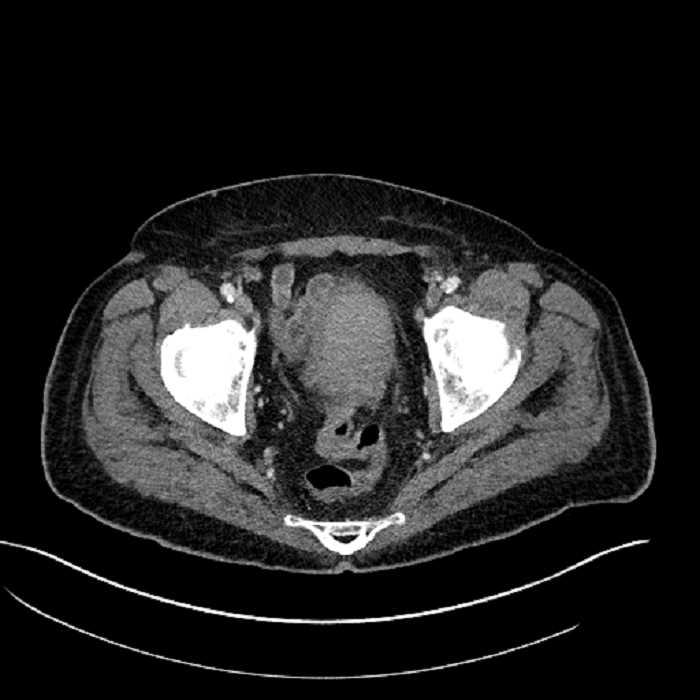

Age: 63

Sex: Male

Indication: Abdominal pain

• Large fluid density structure in hepatic segments 7 and 8 measuring 10 x 7 x 7 cm with internal septation and circumferential ill-defined low density compatible with edema

• Peripherally enhancing subcapsular collections along the anterior margin of the left hepatic lobe measuring 3 x 1 cm and 2 x 1 cm

• Clearly marginated fluid density structure in segment 7 and several other scattered tiny hypodensities, which likely represent cysts

• Mild mural thickening of a segment of the sigmoid colon with adjacent fat stranding and a 1.5 cm fluid and gas collection along the tip of an inflamed diverticulum

• Loss of the normal fat plane between this collection and adjacent loops of small bowel, which demonstrate mural thickening

• High grade stenosis of the left common iliac artery, with the left internal and external iliac arteries remaining patent

• Ankylosis of both sacroiliac joints

• Hepatic abscess

Acute sigmoid diverticulitis complicated by a small contained perforation and a large abscess in the right hepatic lobe. Additional small subcapsular abscesses along the anterior margin of the left hepatic lobe.

Additionally, loss of the normal fat plane between the peridiverticular collection and adjacent thickened loops of small bowel raises the potential for an enterocolonic fistula.

High grade stenosis of the left common iliac artery. The left external and internal iliac arteries are patent.

Hepatic abscess showing the double target sign with low density internally surrounded by a thin inner enhancing rim (red arrow) and ill-defined outer low density rim (yellow arrow). Blue arrow indicates an internal septation. Red arrows: additional smaller subcapsular abscesses. Red arrow: focal contained perforation associated with diverticulitis.